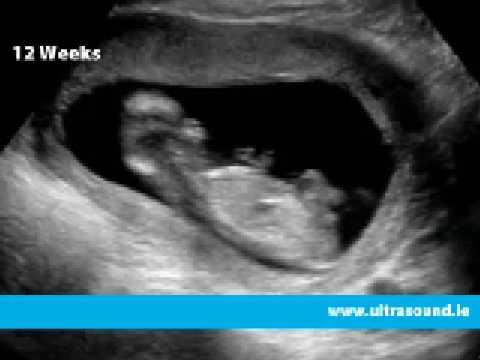

It's not usual to have a dating scan early in your pregnancy to work out how many weeks pregnant you are and your due date . However, you may need a scan in early pregnancy if you have complications such as bleeding . Sometimes other scans are carried out to check the growth of your baby or the position of your baby or the placenta . You will need extra scans if you're carrying twins or if you have had complications in this pregnancy or a previous pregnancy .

The purpose of the scan is to confirm viability, accurately establish gestational age, determine the number of viable fetuses, evaluate gross fetal anatomy and, if requested, assess the NT as part of the risk assessment for aneuploidy . Indications for early pregnancy scans (less than 12 weeks) Indications include:

Dating scan : It is no longer usual to have a scan to work out how many weeks pregnant you are and your due date . Nuchal translucency scan : This is part of first trimester combined screening for Down syndrome and other conditions (read more below) . If you decide to go ahead with this optional screening test, you will be offered a scan between 11 weeks 2 days and 13 weeks 6 days (ideally 12 weeks) .

An early pregnancy dating scan , when compared with scans later in pregnancy, can be more accurate when assessing the expected date of delivery . With maturity, the size of the baby correlates less to its age than in the early weeks . Why would I need a 7 weeks pregnant scan ? To see if one or more babies are present and assess gestational age .

The scan is optional and not everyone will have it . You can discuss whether you want or need a dating scan with your doctor or midwife . A dating scan is usually done to check how many weeks' pregnant you are, but can be done for other reasons, such as if you have had bleeding during your pregnancy or you have had previous miscarriages . If you choose to have a dating scan , it will most probably be your first scan . You will need to get a referral from your doctor or midwife for a dating scan .

Pregnant women should be offered an early ultrasound scan between 10 + 0 and 13 + 6 weeks to establish accurate gestational age . (Grade A recommendation) Ultrasound assessment of embryonic/fetal age ( dating ) uses the following assumptions: